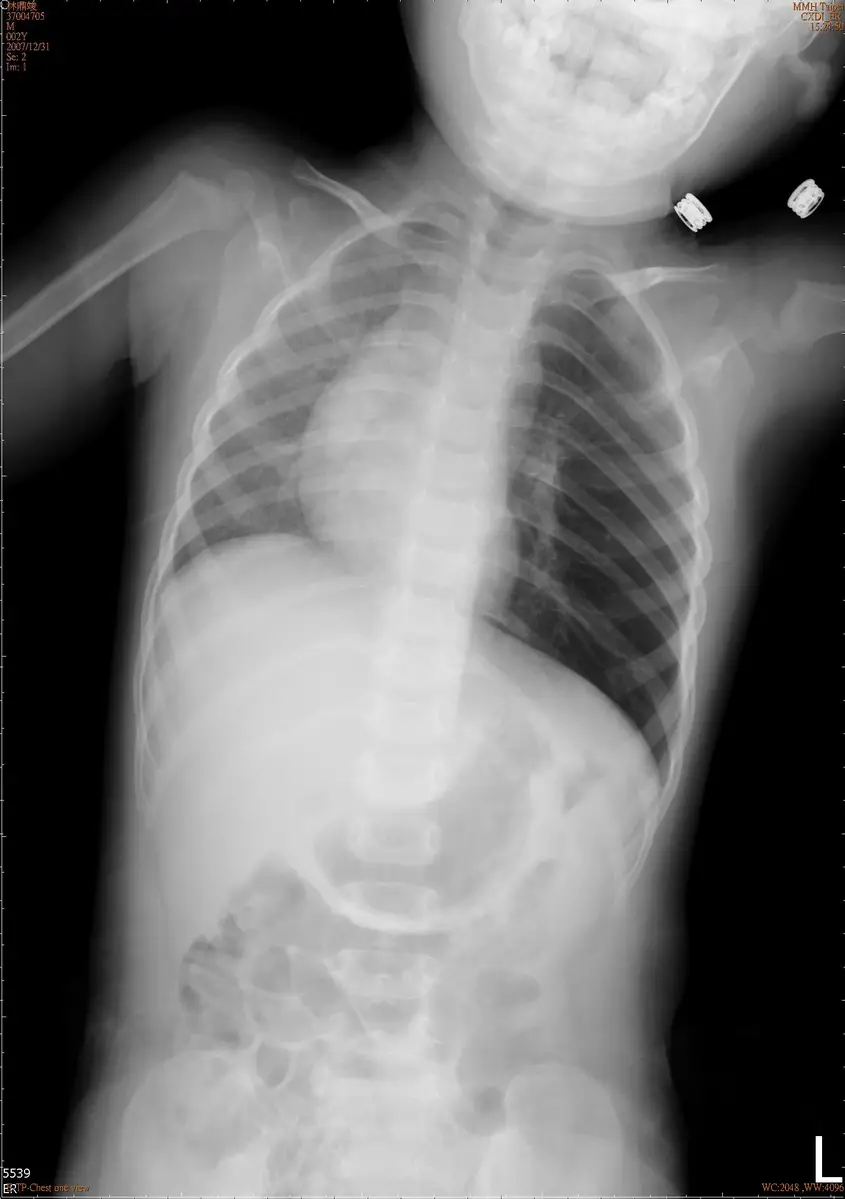

14 個月大的男生,出現咳嗽並有呼吸急促已有 10 天,因為一直沒有發燒,直到媽媽發現他食慾不振的情形才到門診求治,肺部聽診時發現兩側都可以聽到喘鳴聲( wheezing ),左側呼吸音比右側小聲,胸部 X光片檢查如圖所示,下列何者是最有可能的診斷?

胸部 X 光片(前後位)顯示:

- 左側肺葉明顯過度充氣(obstructive hyperinflation):左肺野較右肺野透亮度顯著增加(更黑),肋間隙增寬,左側橫膈膜壓低

- 縱膈向右側偏移(mediastinal shift to the right):心臟及縱膈結構向對側移位,此為受阻肺葉過度充氣所推擠的結果

- 右側肺葉相對正常:右側肺紋路清晰,透亮度正常

- 無氣胸表現:左側無臟層胸膜線(visceral pleural line),不支持氣胸診斷

- 機制:異物位於左主支氣管(left main bronchus)造成「活瓣效應(ball-valve mechanism)」——吸氣時氣體可通過異物旁進入肺部,呼氣時因異物阻擋氣體無法完全排出,導致左肺漸進性氣體滯留

(A) 呼吸道異物:最可能的診斷。14 個月大男嬰、10 天的無發燒慢性咳嗽、雙側喘鳴(因異物可引起反射性支氣管收縮)、左側呼吸音較小聲、X 光顯示左肺過